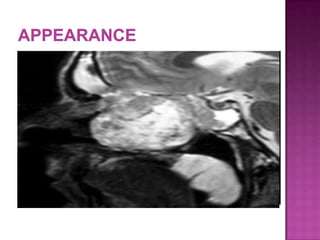

 convoluted cerebriform pattern on T2- or

enhanced T1-weighted images suggests inverted

papilloma as a histologic diagnosis

 Necrosis in a mass with such an appearance

strongly suggests coexistent carcinoma

 columnar pattern is a reliable MRI indicator of IP

and reflects its histological architecture (positive

predictive value of 95.8%)

 combination of this finding with the absence of

extended bone erosion allows for the confident

discrimination of IPs from malignant tumors